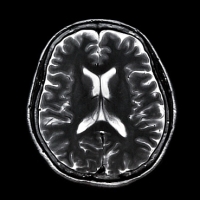

A kutató munkatársaival 40 önkéntes résztvevő agyáról készített MRI-felvételeket, majd a résztvevőknek egy olyan tesztet kellet kitölteniük, amelyből kiderült, hogy mennyire képesek a másik ember mentális állapotát és érzelmeit átérezni és megérteni. Végül a kutatók megkérdezték az önkéntesektől, hogy az elmúlt hét nap folyamán hány emberrel kerültek valamiféle szociális kontaktusba.

Az elemzések során kiderült, hogy a nagyobb szociális hálózattal rendelkező résztvevőknek – akiknek több ismerősük van a Facebook közösségi portálon – nagyobb méretűre nőtt az orbitális prefrontális agykérgük. Ez az agyi terület közvetlenül a szemüreg mögött helyezkedik el, és elsősorban a szociális viselkedésért, valamint a másokkal való interakcióért felelős, pontosabban a szociális jelzések értelmezéséért, az arckifejezésekért, valamint az arcok és a nevek megjegyzéséért. „A prefrontális agykéreg orbitális része kifejezetten az érzelmekért és a jutalmazásért felelős” – tette hozzá Dunbar.